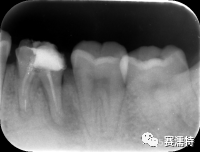

C-Root SP是預混合的、可即刻應用的、可注射的、遇水凝固的硅酸鹽類生物活性陶瓷糊劑材料,主要成分為硅酸鍶、氧化鋯、磷酸鈣、氫氧化鈣,用于根管的密封和永久充填,適合單尖法、側壓法和熱牙膠法。 C-Root SP為世界口腔醫生提供一個“鍶生物陶瓷”的新選擇! >>>